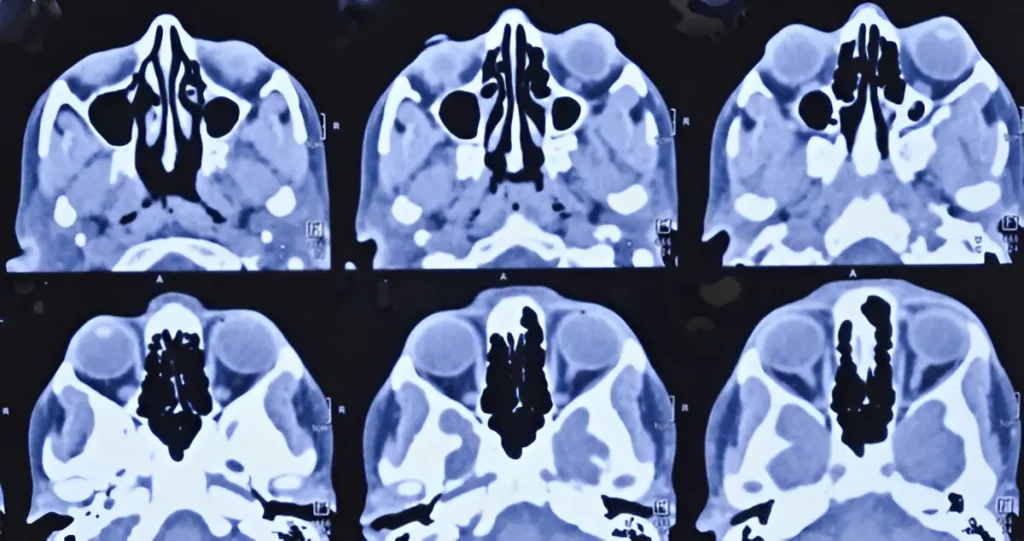

CT PNS in Navi Mumbai | Henotic Diagnostics

Looking for a reliable CT PNS in Kharghar? At Henotic Diagnostics, Kharghar, we provide advanced CT Paranasal Sinus scans for accurate detection of sinusitis, nasal blockages, polyps, and other sinus disorders. Moreover, our expert radiologists ensure safe, quick, and detailed imaging using low-radiation technology. In addition, the scan helps ENT specialists plan effective treatments. Therefore, choosing Henotic Diagnostics means timely diagnosis, trusted reports, and patient-focused care. Book your CT PNS scan in Kharghar today for precise results.